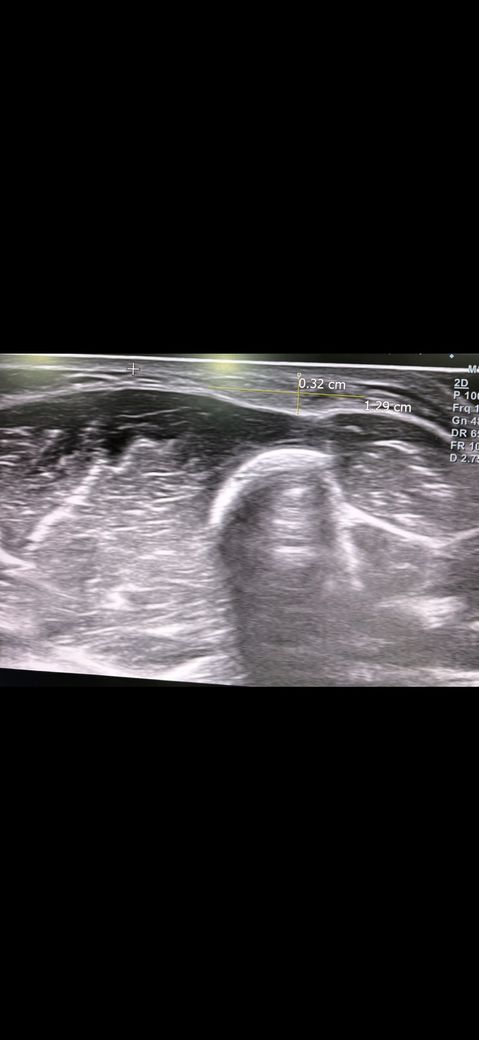

예전에 병원에서 팔에 동글동글하게 두 군데 정도 뭐가 만져지길래 초음파 사진을 찍고왔습니다.

해당 병원에서는 지방종같다고 하셨는데 생긴지 3년은 지난 것 같은데 계속 신경쓰이고 걱정이 되는데 사진의 종양이 지방종이 맞을까요?

• 2번 째 사진

초음파의 경우 정확한 진단보다는 양성 내지 악성 양상을 보는 검사 중 하나라고 생각해 주시면 좋고, 보통은 지방종의 경우 균질하고 경계가 명확한 모양을 띠고 있어, 질문자님의 사진상으로 볼 때에는 지방종일 가능성이 있겠습니다. 휴미라의 부작용으로 지방종을 유추하기에는 아직까지 연구된 부분이 없어서 부작용으로 보기에는 어려울 것으로 사료됩니다.